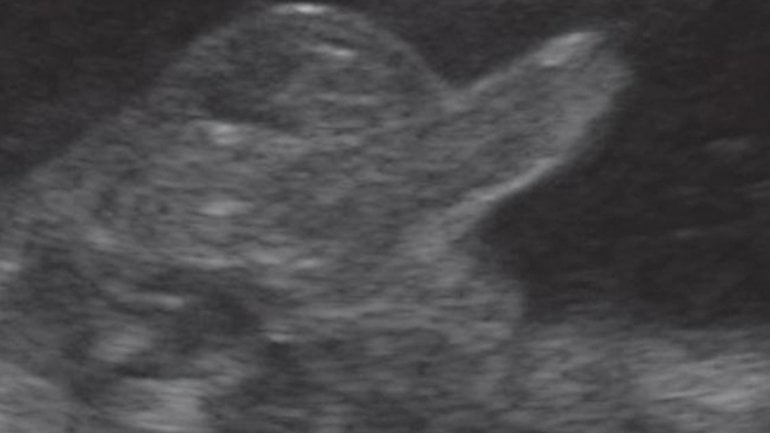

Ultraschall 8. SSW

Der Embryo misst jetzt etwa 15 Millimeter. Zur Orientierung: Der Embryo ist von vorne zu sehen, der Kopf liegt links im Bild. Arm- und Beinansätze lassen den Embryo wie einen kleinen Teddybären aussehen. Auf dem bewegten Ultraschall sind in dieser Woche die ersten, noch unkontrollieren Bewegungen zu erkennen.